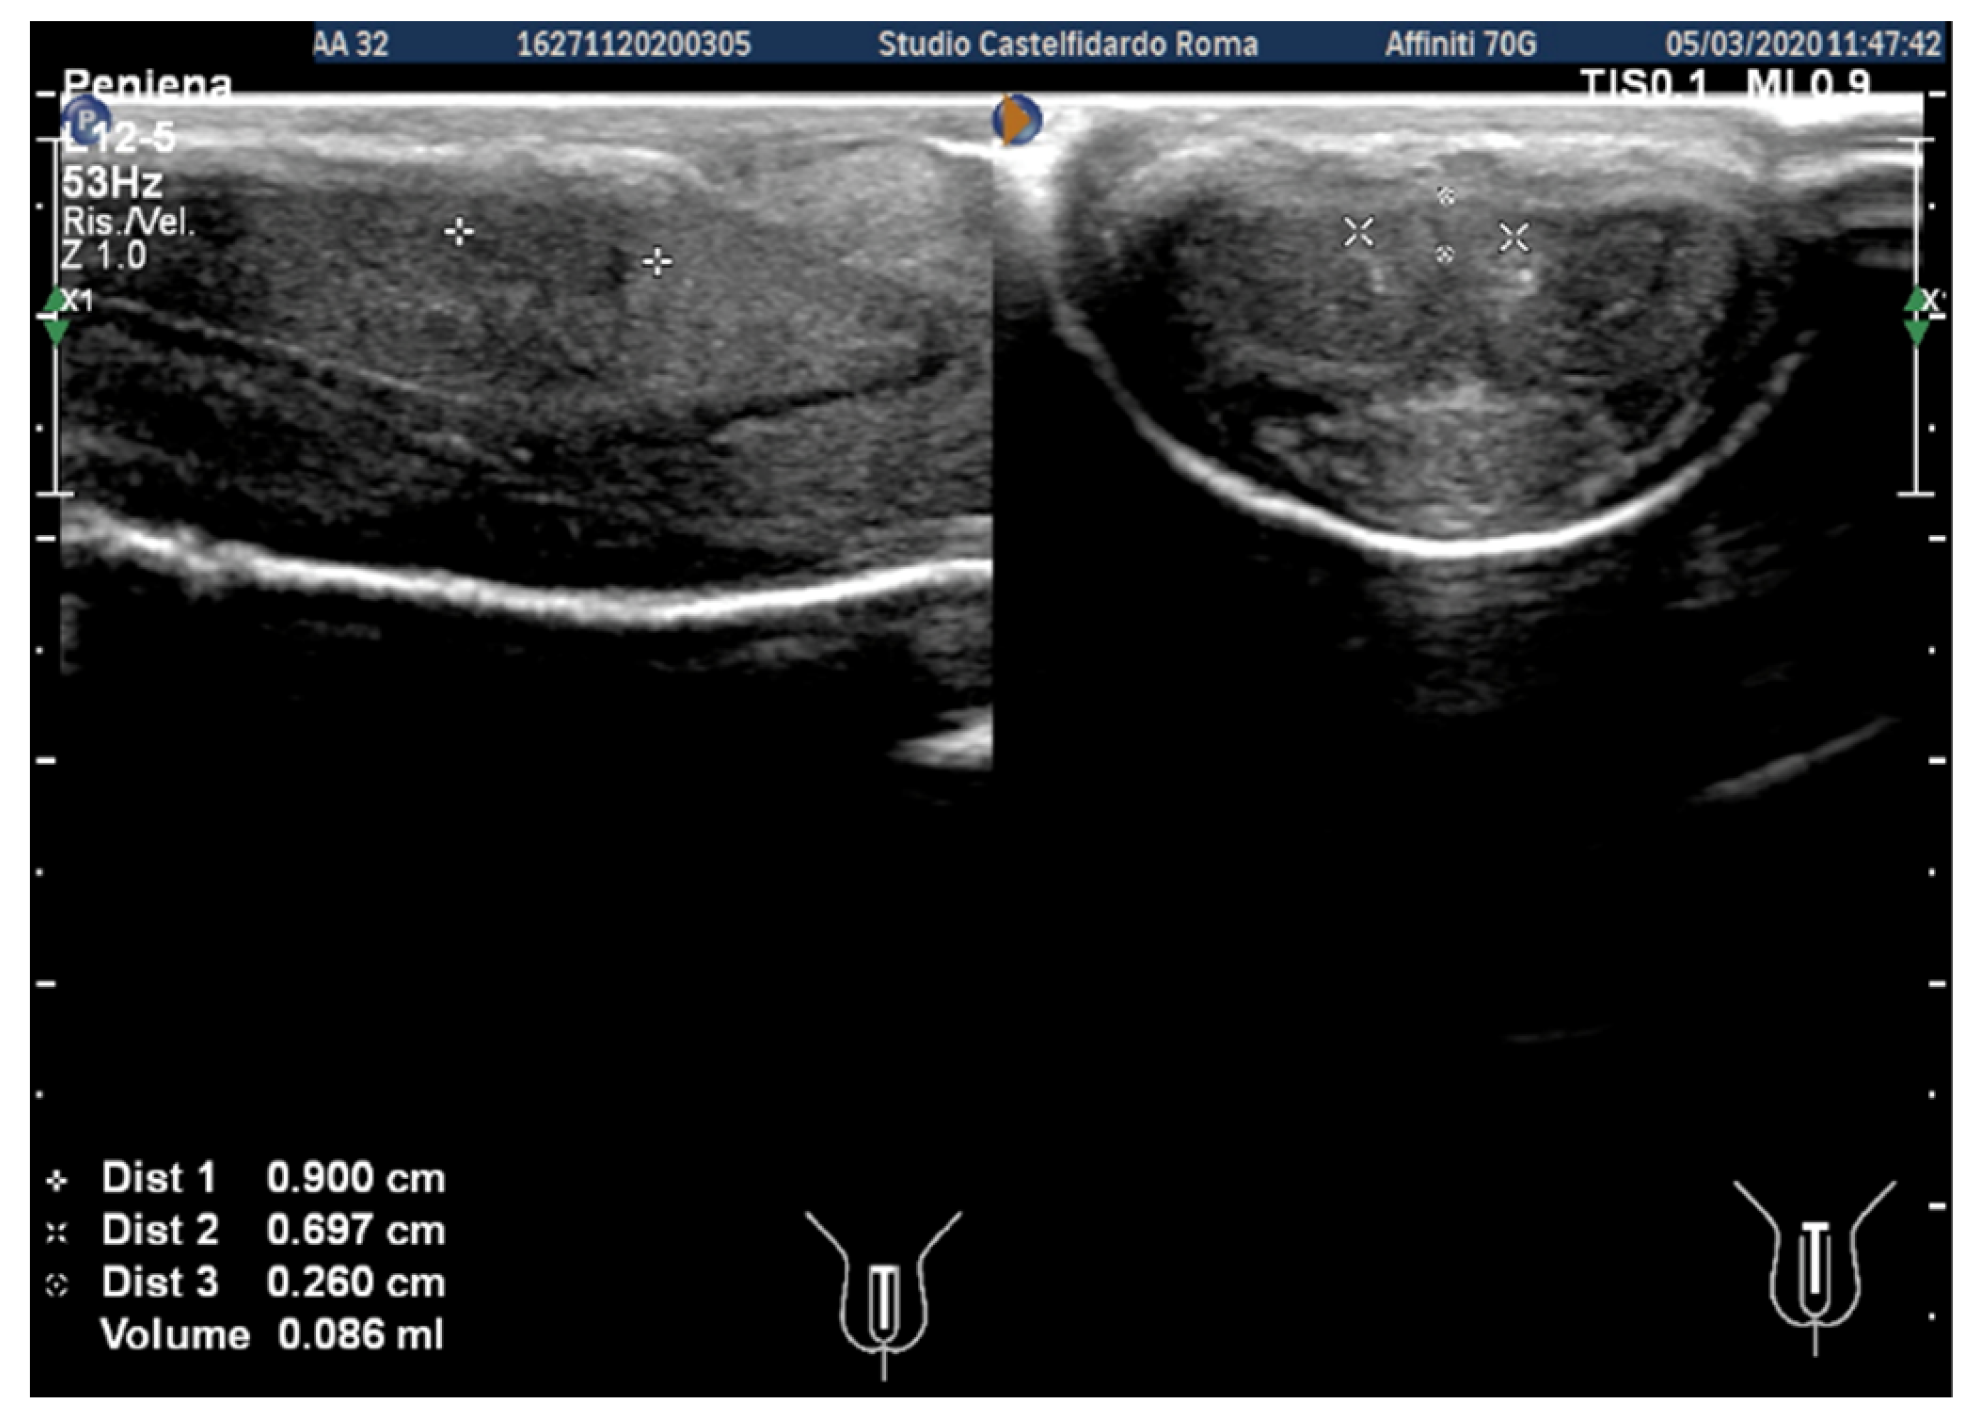

| 1 | 31 years | Chronic prostatitis and associated anxious and depressive state. | Distal third | (A) 15.1 × 12.1 × 3.7 mm volume = 353 mm3 (B) No plaque detected | (A) 10-degree ventral curvature + 15-degree left curvature (B) None | VAS score = 8 Pain disappeared after 12 months | 26 > 27 | 30 months | Orally: propolis 600 mg + bilberry 160 mg + silymarin 400 mg + ginkgo biloba 250 mg + L-carnitine 1000 mg + coenzyme Q10 100 mg + Boswellia 200 mg + Vitamin E 30 mg/daily/for 30 months + topically: diclofenac gel 4%/2× daily for 30 months Note: The patient refused periplaque penile injections with pentoxifylline |